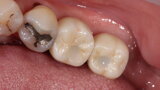

Fig. 13: Implant crowns in situ.